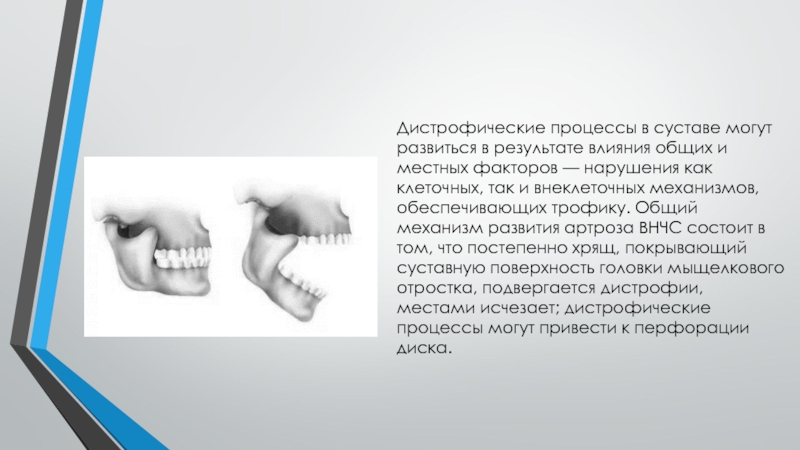

Дистрофические заболевания внчс презентация - 89 фото